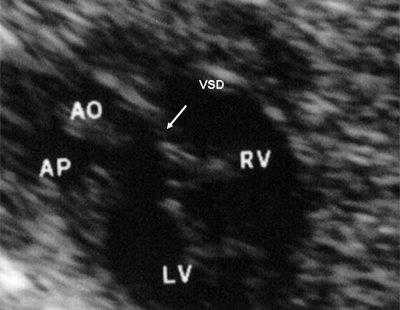

Антенатально при равных величинах давления в желудочках сердца и в предсердиях объемной перегрузки не возникает. В связи с этим ни один из эхокардиографических гемодинамических признаков, используемых у детей и взрослых, не выявляется у плода. К эхокардиографическим проявлениям порока антенатально относится только прямой признак - перерыв ультразвукового луча в области дефекта. Размеры сердца, соотношение размеров желудочков сердца не отличаются от нормы (рис. 5).

Рис. 5. Четырехкамерное сечение сердца плода. Стрелкой указан первичный дефект межпредсердной перегородки (АVS).

В равной степени это относится к дефекту межжелудочковой перегородки (рис. 6), простой форме транспозиции магистральных сосудов (рис. 7, 8), транспозиции магистральных сосудов с дефектом межжелудочковой перегородки (синдром Тауссиг - Бинга) (рис. 9), общему желудочку (рис. 10), общему артериальному стволу (рис. 10), двойному отхождению сосудов от одного из желудочков сердца (рис. 11).

Рис. 6. Дефект межжелудочковой перегородки. Длинная ось сердца. Стрелками показан дефект межжелудочковой перегородки.

LV и RV - левый и правый желудочек, АР - легочная артерия, АО - аорта, VSD - дефект межжелудочковой перегородки.